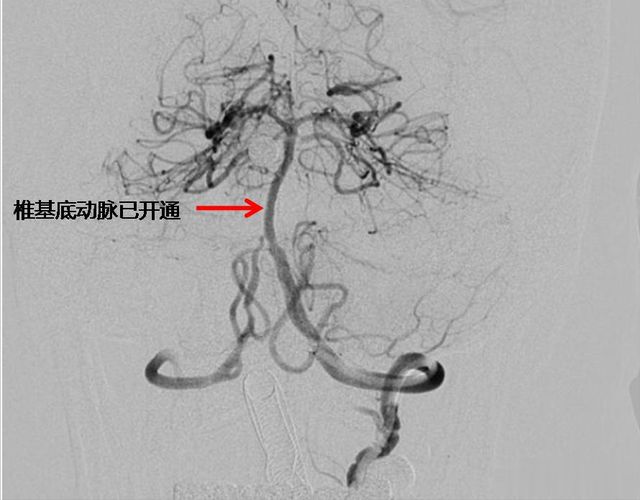

边复苏边手术!10分钟打通闭塞椎基底动脉,74岁老先生成功获救